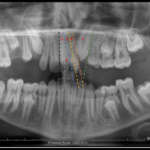

Intercettare l’inclusione del canino superiore mediante estrazione precoce del canino deciduo Premium

Viene valutata clinicamente la validità dell’estrazione precoce dei canini decidui in dentatura mista per prevenire l’inclusione dei canini permanenti. Lo studio si è svolto analizzando le ortopantomografie di quattro pazienti per un totale di sei canini, a distanza di circa 14 mesi dopo l’estrazione del canino deciduo.